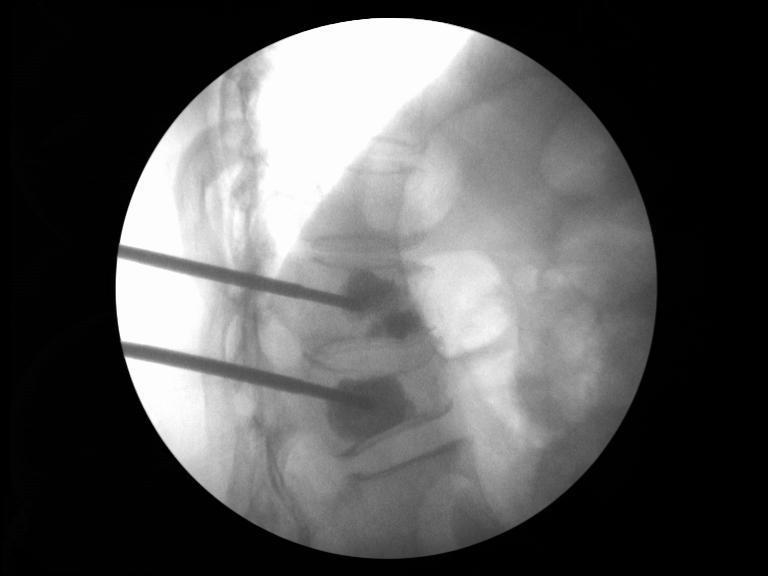

开展的多种手术治疗:各种复杂四肢骨干及关节内骨折开放复位内固定术、各种微创技术治疗各种肢体骨折(肱骨骨折、胫骨骨折、股骨近端骨折Mippo技术内固定及粗隆部骨折PFNA内固定)、骨盆髋臼骨折的内/外固定术、外固定架治疗骨不连、骨缺损、骨延长、骨病的病灶清除、植骨及固定术、各种畸形的矫正及功能重建术等;并开展各类内固定取出术。

切开复位内固定